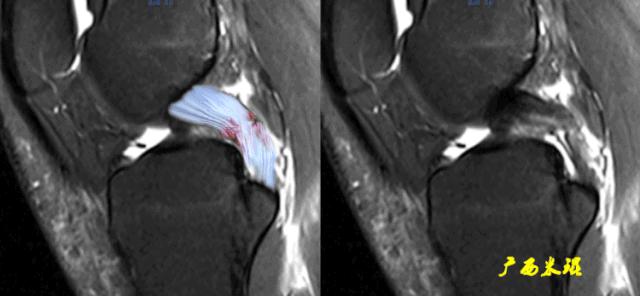

腘肌腱是后外复合体的重要组成部分,所以腘肌腱的损伤也常常与PCL损伤相关,腘肌腱在MRI上显示也是非常清楚的,下面的这张膝关节MRI矢状面除了清楚的显示仪表板征之外,可以见到后方的腘肌腱出现高信号,周围组织水肿,这些征象都应该考虑有PCL损伤的可能。

膝关节矢状面可以见到损伤的腘肌腱,不同的横断面也能够显示腘肌腱,下面的膝关节横断面显示腘肌腱损伤移位,肌腱内出现高信号,边缘不清晰,髁间窝还见到PCL连续性中断。